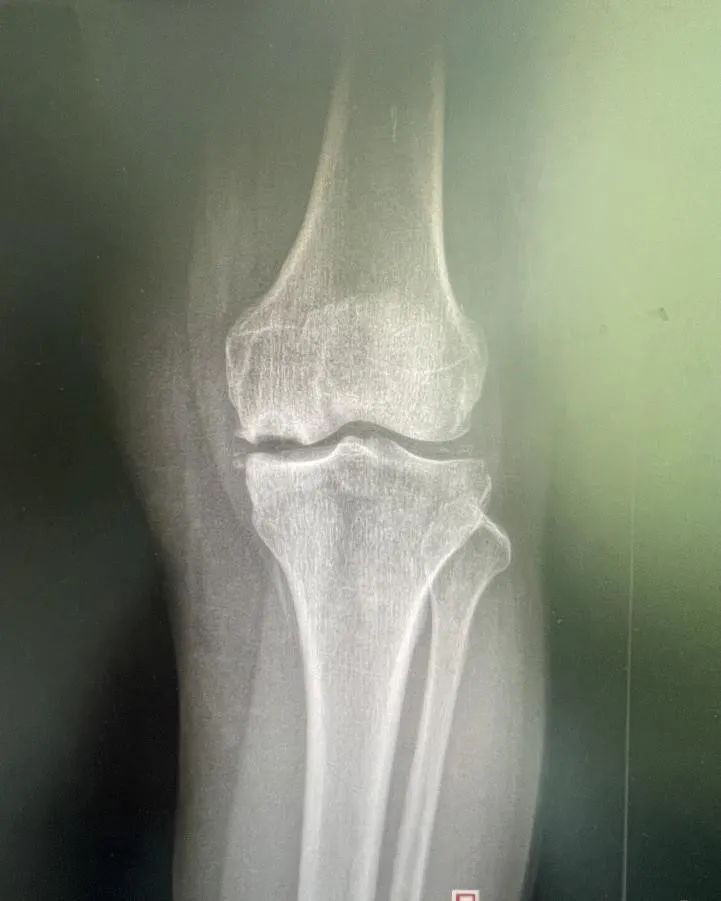

老年膝关节疼痛都是骨头磨损了吗?小心是骨头自己坏了

“膝关节里像有“钉子”一样,走路特别困难”“关节肿胀疼痛的难受”“吃了很多药,也不管用了”老年膝关节疼痛通常被认为是由于骨头磨损所致,但实际情况可能更为复杂。